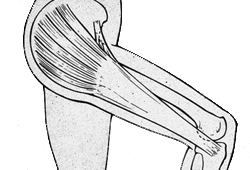

Anatomy of iliotibial band. IT band, iliotibial band; Gluteus max, gluteus maximus; TFL, tensor fascia lata

From the personal collection of Dr J.C. Mak